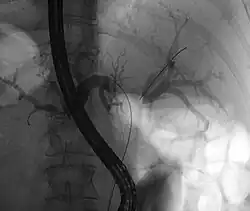

ERCP: stents placed in the left and right bile duct. At the right, the contrast that has been given before is already well-drained, making the bile ducts clearly recognizable.